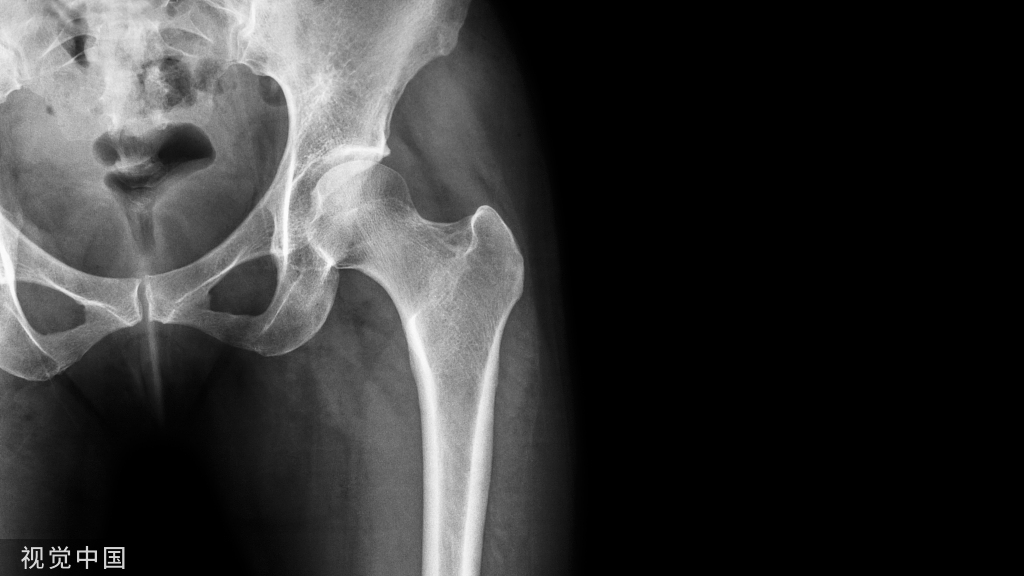

髋关节置换术是一种使用假体替换骨关节的治疗方式,主要涉及的部位是股骨部分、髋臼部分,通过骨水泥、螺钉等固定在患者的骨质上,取代其病变部位,从而重建髋关节的功能。

股骨头坏死、骨性关节炎、创伤性关节炎均能通过髋关节置换术治疗,常见的髋关节置换术中人工关节假体所用的材料以前多用不锈钢,目前绝大部分都是医用钛合金和陶瓷组合,但部分患者术后会发生严重疼痛及假体松动问题。